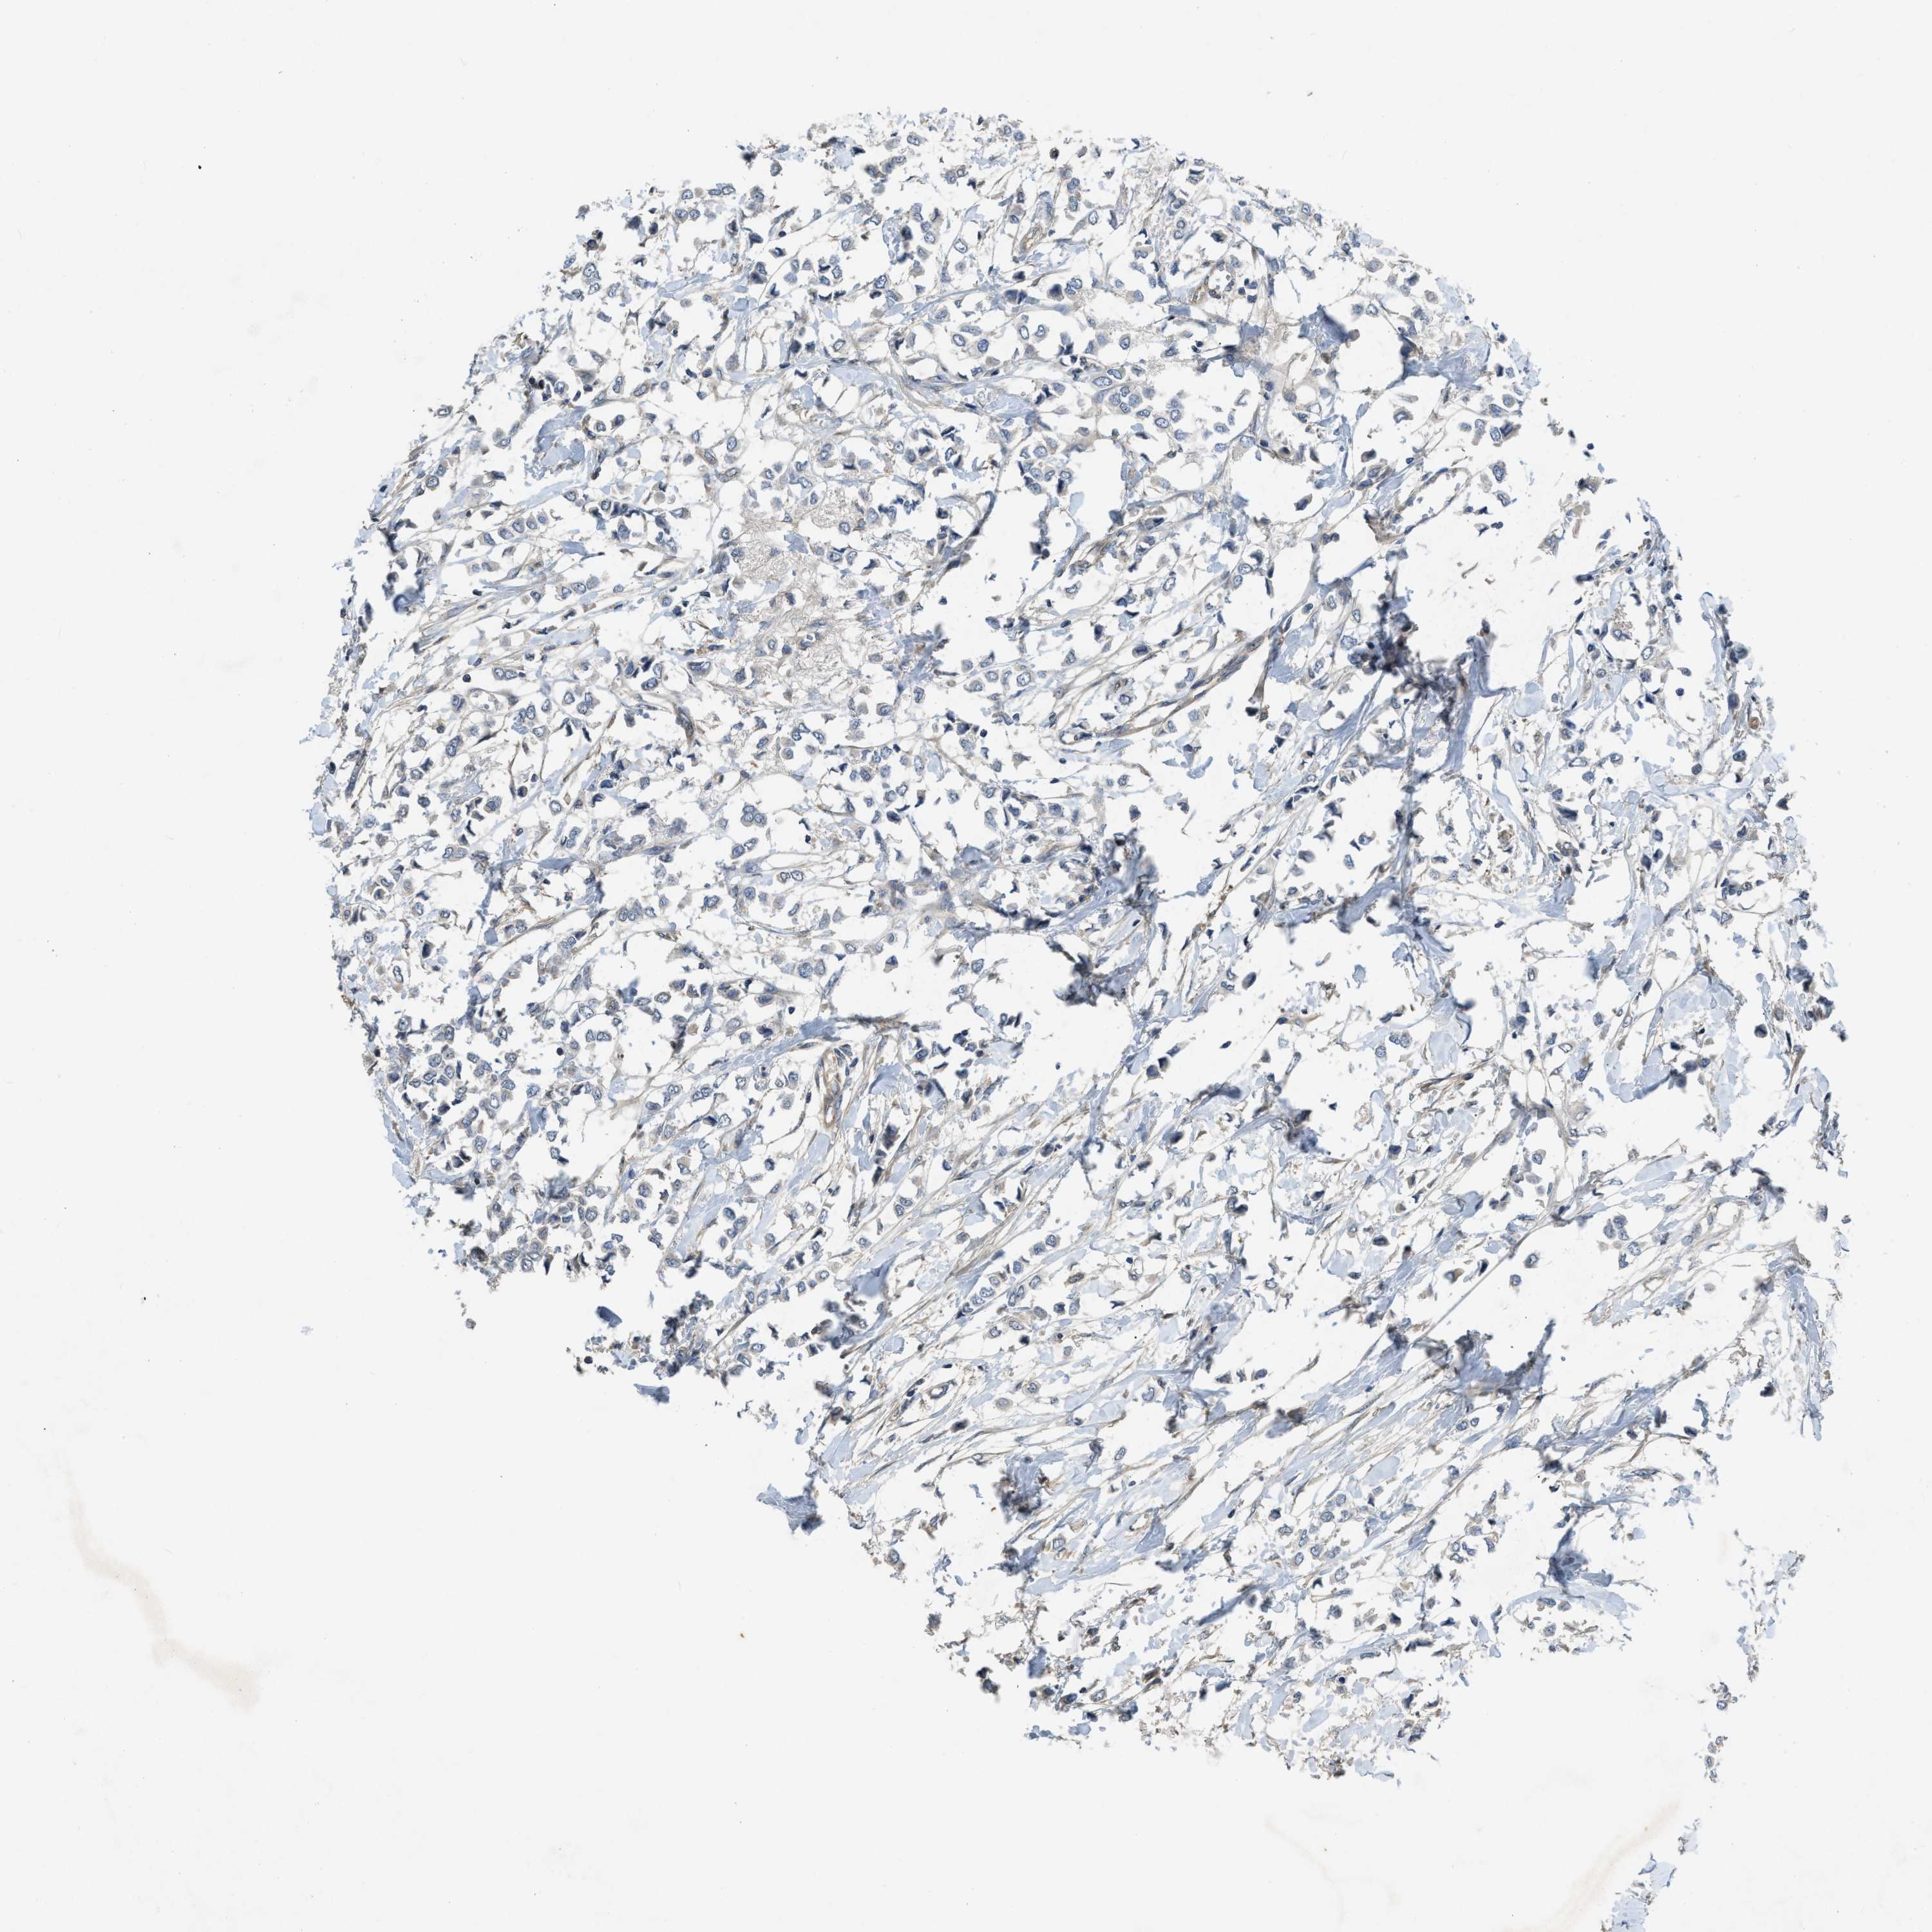

CANCER BREAST CANCER Show tissue menu

BRCA TCGA BRCA VALIDATION PROTEIN EXPRESSION